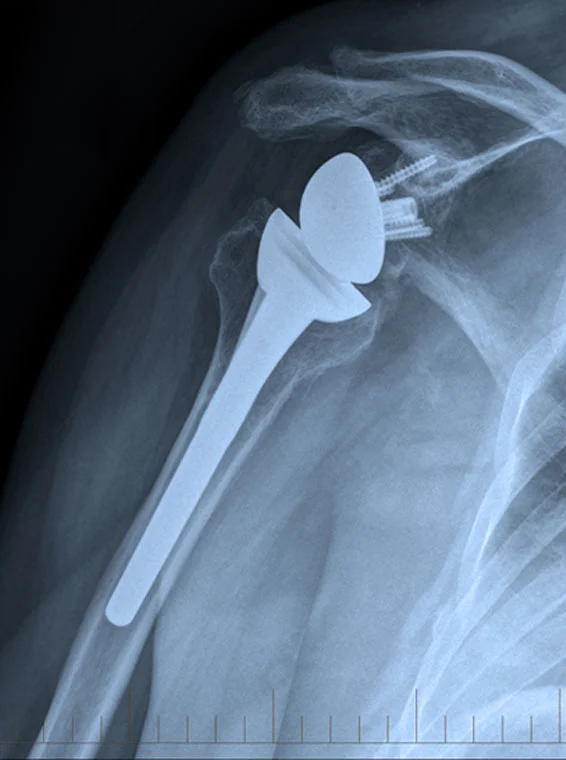

Shoulder replacement surgery is becoming more common as a method of treatment for arthritis of the shoulder joint.

Shoulder arthritis is less common than other forms such as hip and knee arthritis as the shoulder is not a weight bearing joint. However due to the ageing population conditions such as osteoarthritis of the shoulder and other conditions such as tears of the rotator cuff which can ultimately go on to cause arthritis within the shoulder have become more prevalent in our community. Sometimes shoulder replacements are used to manage fractures of the shoulder.

Shoulder replacement surgery restores function and treats pain by removing the arthritic parts of the joint.

Arthritis is a process which results in loss of the articular cartilage or the lining of the joint. In the process of the cartilage being lost or if the cartilage has been completely lost, inflammation is generated by the damaged cartilage or damaged bone. This inflammation is an attempt at a healing response in the joint but due to the nature of articular cartilage it does not regenerate. Hence usually there is progression of degenerative changes in a joint over time. With progression of the damage there is often an increase in pain and also an increase in stiffness. Stiffness causes functional limitation as the shoulder is normally a very mobile joint.

With age loss of cartilage can occur in the shoulder joint. It is also possible for the rotator cuff tendons over time to wear out. The tendons in the body generally have poor blood supply and are not good at healing and while they are strong they tend to be prone to wear. The tendons in the shoulder joint are susceptible to tears. The tears will not heal and tend to increase in size with time.